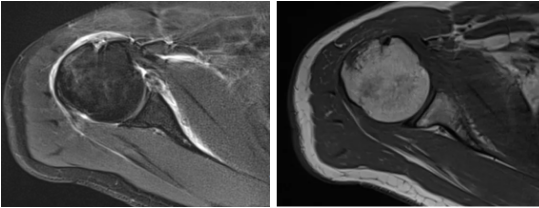

病例1

病史摘要:男性,44歲,跌傷致右肩關(guān)節(jié)疼痛數(shù)天,活動不利。

MR圖示:右側(cè)肱骨后外上方局部骨皮質(zhì)塌陷,并鄰近皮質(zhì)下斑片狀壓脂高信號影(箭頭);前盂唇撕脫,前方見低信號游離骨片影(三角形)。